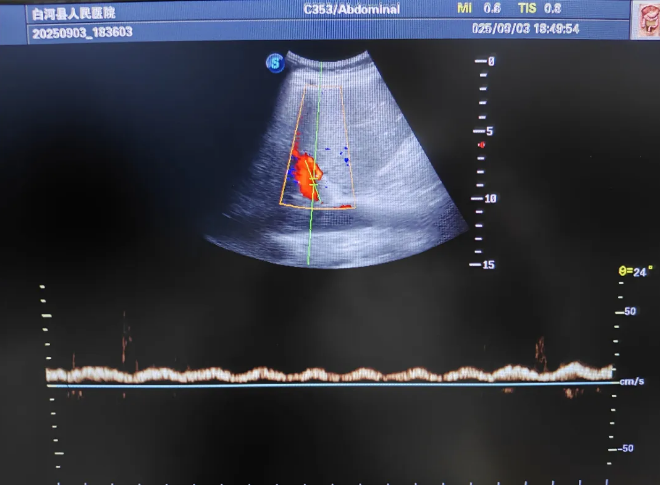

探头轻放,心脏功能良好,血管容量也正常。超声像一只“透视眼”继续向下探索,一个充盈的膀胱出现在屏幕上。

“大爷,您以前有前列腺增生的毛病吗?”王晓宇医生问道。老人无力地点点头。

真相大白!不是药物,不是原发病,而是最直接、也最容易忽视的问题——尿路梗阻!

前列腺增生堵住了生命的“下水道”,尿液排不出去,毒素反流入血,引发了肾后性肾衰竭。